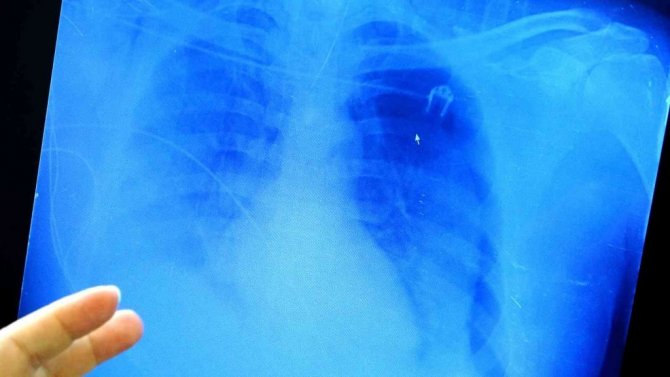

"Hiç akciğer dokusu kalmamış"

40 yaşında aşısız entübe olan bir hastanın akciğer filmini inceleyen Özkaya, "Özellikle aşısız genç grupta çok ciddi akciğer tutulumları görmeye başladık. Önceki dönemlerde aldığımız bu tedavilerdeki başarıları bu yeni mutant virüsle aşısız gençlerde maalesef alamıyoruz. 40 yaşında oldukça genç olan bu hastamız aşının yan etkilerinden korktuğu için aşı olmamış. Ciddi akciğer tutulumu ile bize geldi. Şu an hiç akciğeri yok. Herkes evde kendi ailesinden bir hastalandığı zaman bu işin ciddiyetine varıyor. Biz istiyoruz ki ailenizden biri bu hale gelmeden işin farkına varmanızdır. Hala tedavisini bulamadık. Tedavilerle hastaları kurtarmaya çalışıyorduk ama şu an yeni virüsler tedaviye yanıt vermeyen ciddi akciğer tutulumları yapıyor. Bu genç 40 yaşındaki hastamızın hayata tutunmasını sağlamaya çalışıyoruz" şeklinde konuştu.